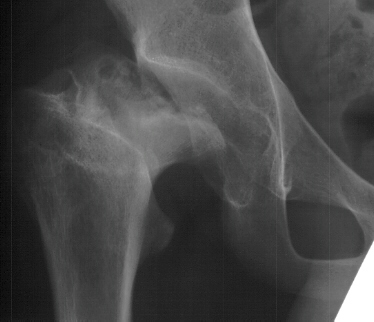

- Hospital Day 6: Respiked to 103.4. R hip Xray showed a defect in proximal

medial metaphysis, Possible osteomyelitis. The child was than taken to

the operating room for Incision & Drainage of Right hip via anterolateral

approach with suction irrigation system (seropurulent fluid drained).

- Post Operative Day 7: Drains removed. Respiked to 101.6. R hip Xray:

suggestion of demineralization of proximal metaphysis. The hip was reaspirated

- Post Operative Day 18: R hip Xray: subluxation of R hip, possible metaphyseal

lucency consistent with osteomyelitis. Taken to OR for repeat I & D

- 2 month Office Follow Up: Rt hip Xray: progressive destruction of capital

femoral epiphysis, cystic changes in metaphysis consistent with AVN.